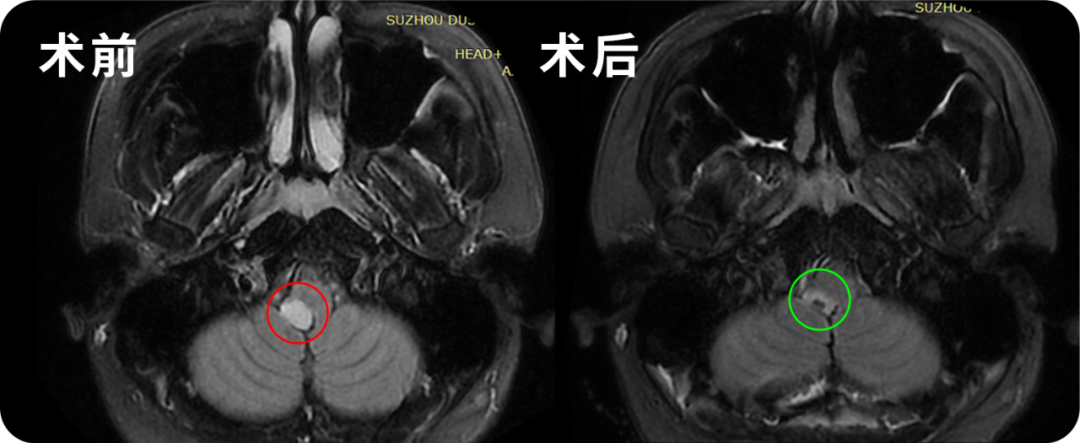

33岁男性•脑干-桥臂胶质瘤

◉患者情况:精通多国语言,本该在热爱的领域发光发热的他却查出脑干桥臂位置疑似有一个低级别胶质瘤,大小17mm。由于位置深,手术风险大,医生不建议手术及活检。早在2022年,韩先生由于头晕、右侧脸麻、面瘫查出这个病灶,怀疑脱髓鞘病变。经激素治疗一个月,症状并无好转。无奈持续保守观察至2023年7月,MRI复查提示病灶增大,MRS提示疑似肿瘤指征,考虑低级别胶质瘤。得到这个复查结果后,韩先生内心的希望全部落空了,狠狠地给了他一击。但他并没有被击退,因为他还年轻,还有很多事情需要去做。听闻巴教授9月来华的消息后,选择远程咨询巴教授。

◉治疗过程:9月29日,在苏州独墅湖医院,巴教授顺利为其顺利手术。

◉术后情况:术后1天顺利转出ICU,巴教授查房,韩先生说话正常。术后2天查房,感觉状态很好。术后4天查房,可以下地走路并给教授弹奏一曲表示感谢。